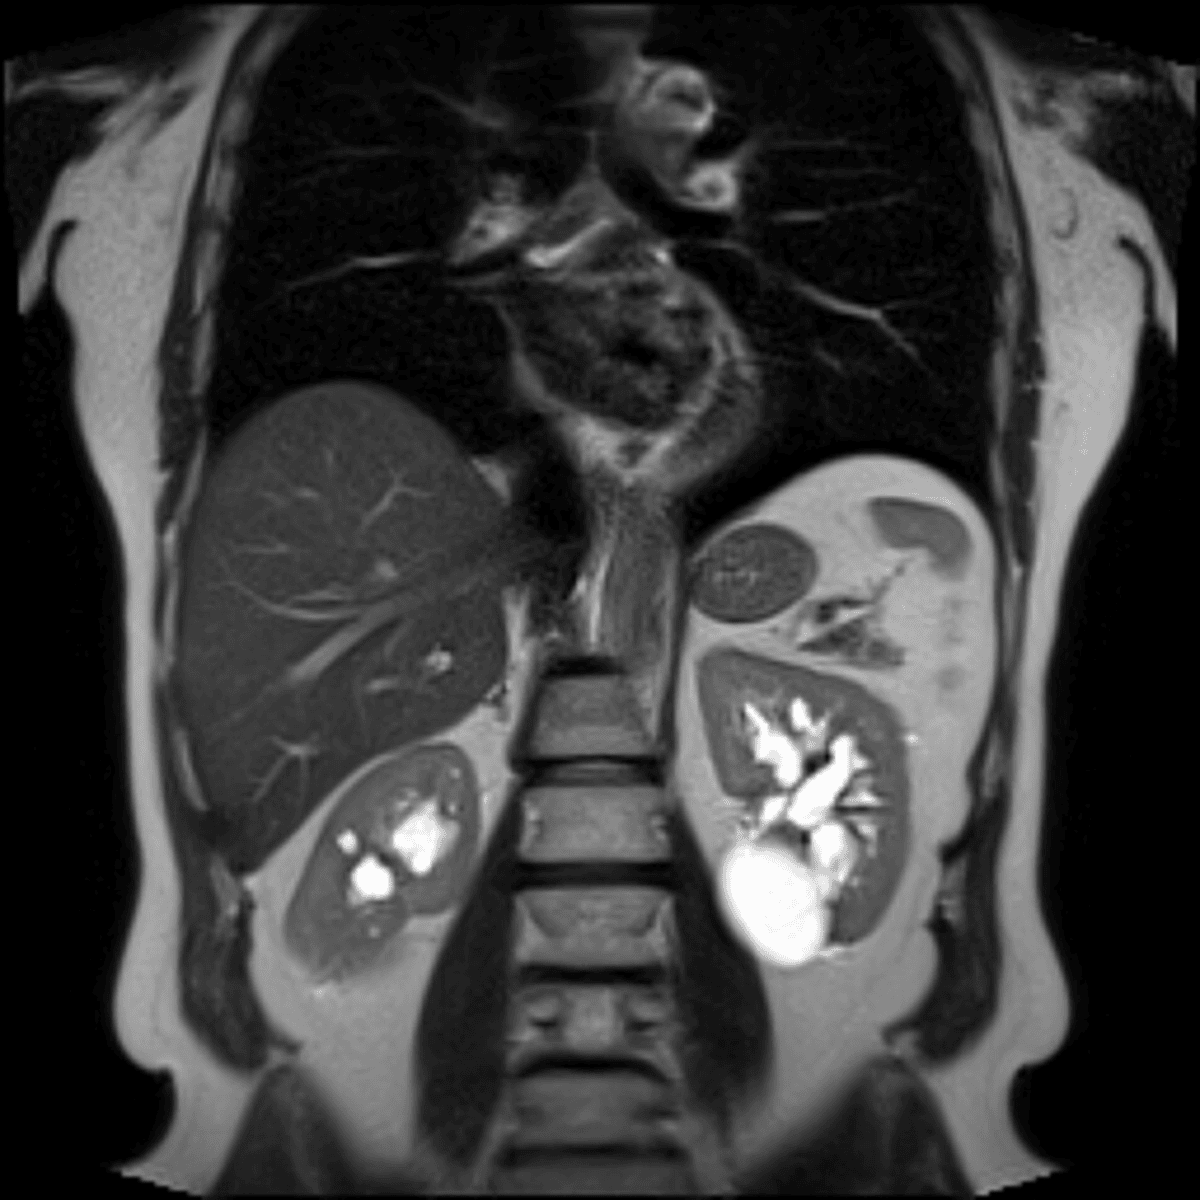

The pancreas is a long, flat gland that sits tucked behind the stomach in the upper abdomen. Its main function is to produce enzymes that help with digestion and hormones that help regulate the way the body processes sugar. Although the body and tail of the pancreas are absent, the pancreas has a normal appearance. The absence of the body and tail are reflective of your known history of situs inversus.